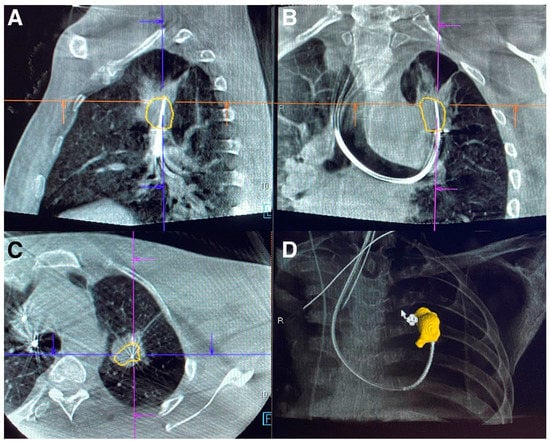

- Pritchett, M.A.; Schampaert, S.; de Groot, J.A.; Schirmer, C.C.; van der Bom, I. Cone-Beam CT With Augmented Fluoroscopy Combined with Electromagnetic Navigation Bronchoscopy for Biopsy of Pulmonary Nodules. J. Bronc.-Interv. Pulmonol. 2018, 25, 274–282. [Google Scholar] [CrossRef] [PubMed]

- Piro, R.; Fontana, M.; Casalini, E.; Taddei, S.; Bertolini, M.; Iori, M.; Facciolongo, N. Cone beam CT augmented fluoroscopy allows safe and efficient diagnosis of a difficult lung nodule. BMC Pulm. Med. 2021, 21, 327. [Google Scholar] [CrossRef]